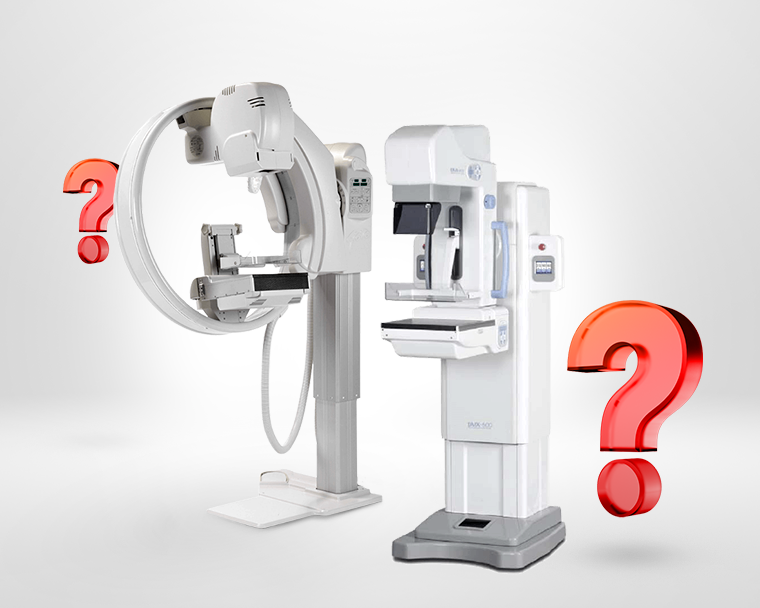

Как выбрать маммограф?

Шаг 1. Аналоговая или цифровая маммография

Исследования молочной железы с помощью рентгеновского маммографа могут отличаться способом записи изображения. По такому принципу все оборудование можно разделить два типа:

- аналоговый маммограф, результат исследования сохраняется на рентгеновской плёнке;

- цифровой маммограф, изображение молочной железы сохраняется в цифровом виде на консоли оператора или рабочем месте рентгенолаборанта для дальнейшей передачи и анализа врачом рентгенологом.

У некоторых производителей рентгеновский маммограф может быть как в аналоговом, так и в цифровом исполнении, например:

С-образный штатив / Кольцевой штатив